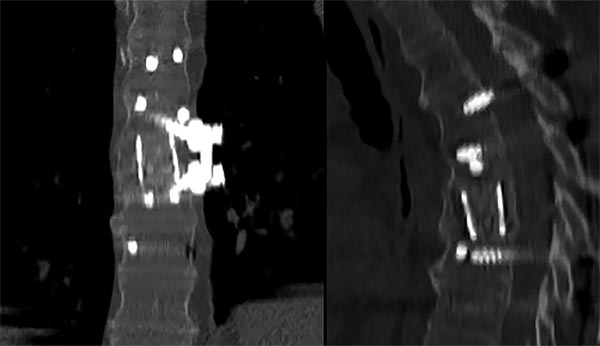

Figura 2:

Caso 24. A y B: Fractura horizontal que compromete cuerpo, pedículo izquierdo y apófisis espinosa de L1 (L1: B1; N1 AOSpine). C y D: Estabilización percutánea T12-L2.

Figura 3:

Caso 24. A: Fractura L1: B1; N1. B: Control 7 meses que evidencia consolidación. C y D: Retiro de osteosíntesis a los 9 meses con buena movilidad en las radiografías dinámicas de control.